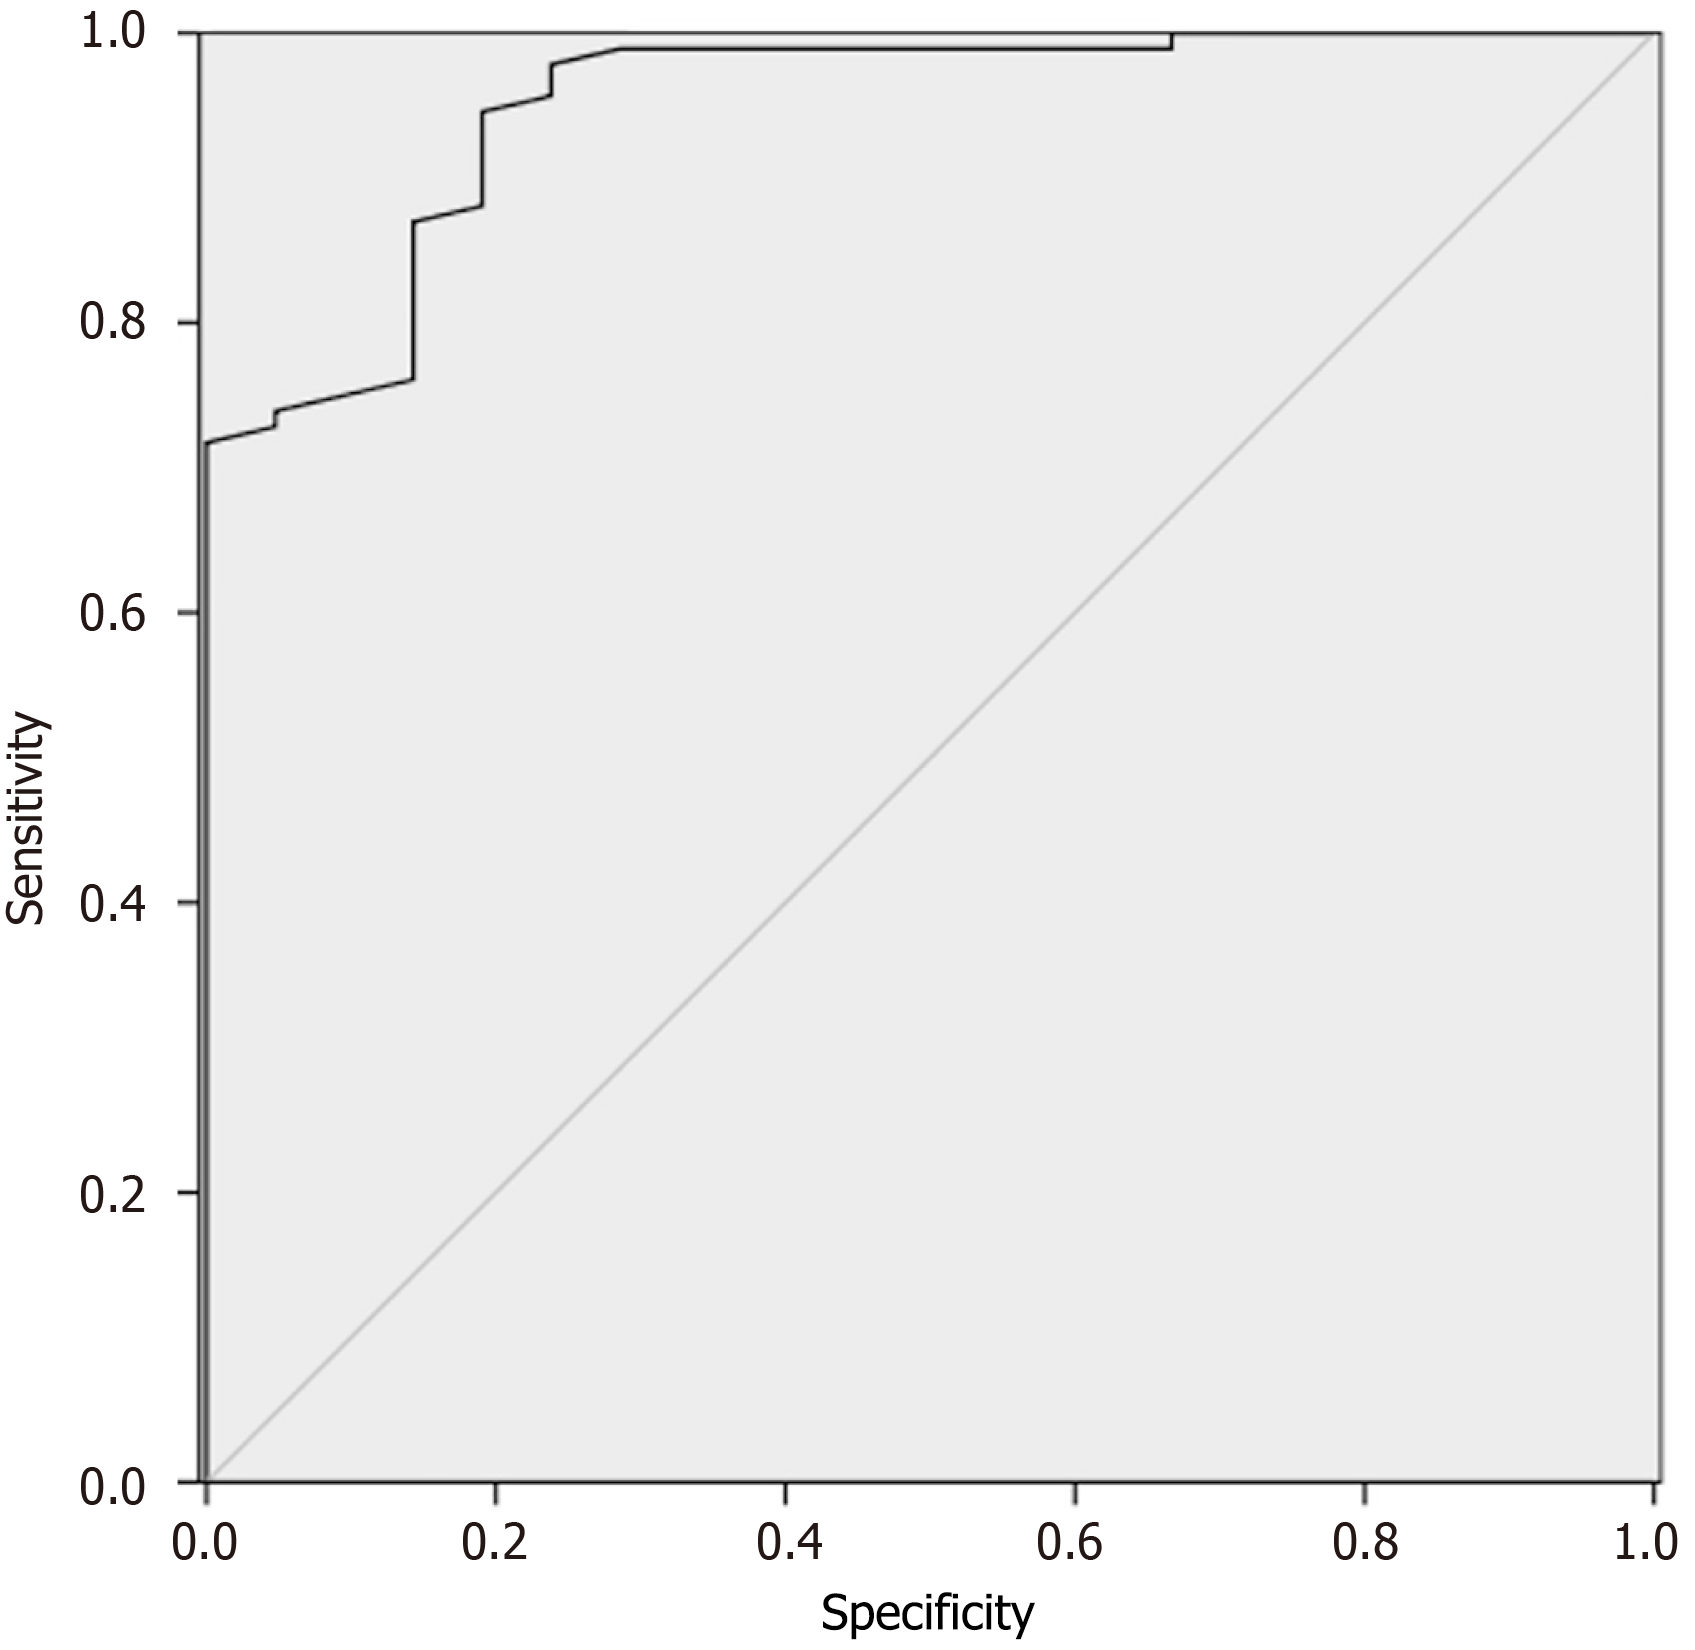

Figure 3 Receiver operating characteristic curve analysis of predictive value of the multivariate logistic regression model.

The area under the curve was 0.950.